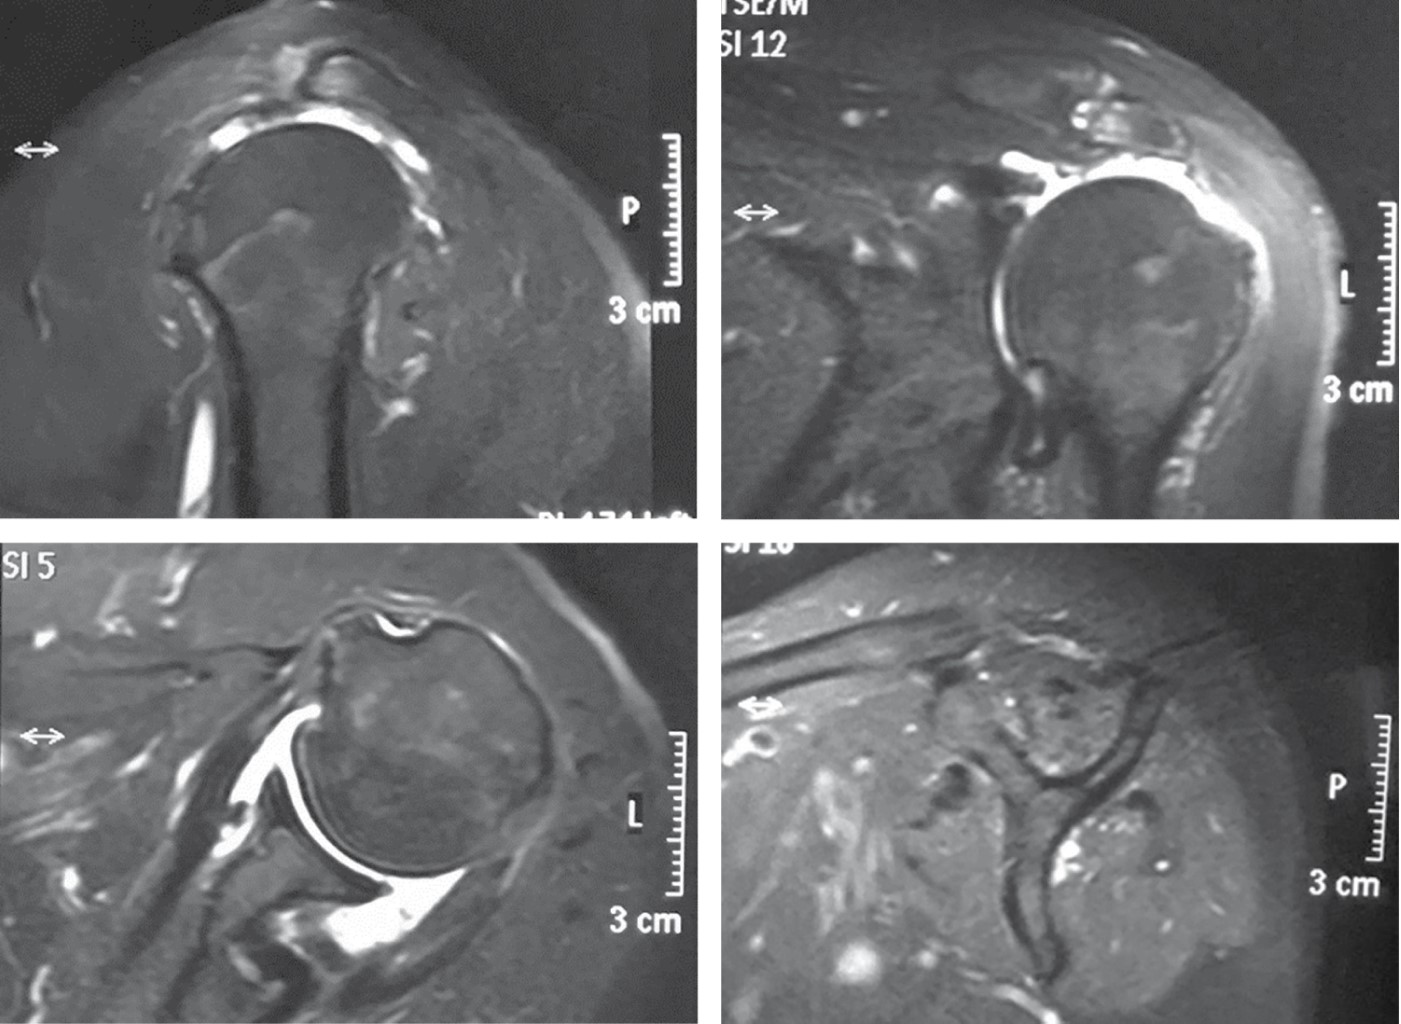

From www.arthroscopytechniques.org

Arthroscopic Superior Capsular Reconstruction for Massive Irreparable Rotator Cuff Repair Rotator Cuff Capsular Pattern according to dutton, capsular patterns are based on clinical findings rather than research; stage 1, the preadhesive stage, demonstrates mild erythematous synovitis. frozen shoulder can develop after a shoulder has been immobilized (held in one position without moving) for a period of time due to surgery, a fracture, or. adhesive capsulitis (also known as frozen shoulder). Rotator Cuff Capsular Pattern.

Arthroscopic Superior Capsular Reconstruction for Massive Irreparable Rotator Cuff Repair Rotator Cuff Capsular Pattern examples include a rotator cuff tear and fractures of your shoulder blade, collarbone or upper arm. stage 1, the preadhesive stage, demonstrates mild erythematous synovitis. The primary way to distinguish rc pathologies from frozen shoulder is to examine the specific. rotator cuff (rc) pathologies. frozen shoulder can develop after a shoulder has been immobilized (held in. Rotator Cuff Capsular Pattern.

From onlinelibrary.wiley.com

Advancement in Arthroscopic Superior Capsular Reconstruction for Irreparable Massive Rotator Rotator Cuff Capsular Pattern stage 1, the preadhesive stage, demonstrates mild erythematous synovitis. frozen shoulder can develop after a shoulder has been immobilized (held in one position without moving) for a period of time due to surgery, a fracture, or. rotator cuff (rc) pathologies. Perhaps that's why the capsular patterns may be different. examples include a rotator cuff tear and. Rotator Cuff Capsular Pattern.